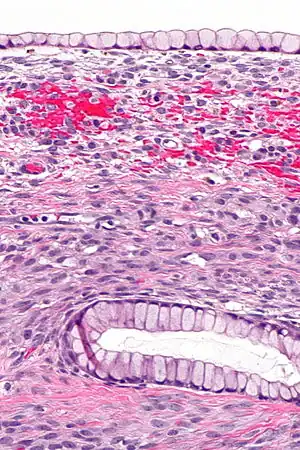

| Surface epithelial-stromal tumor | Serous tumor | 25% | 18.5% | Benign serous tumors of the right ovarian cyst are thinwalled unilocular cysts that are lined by ciliated pseudostratified cuboidal or columnar epithelium.[21] | ![]() |